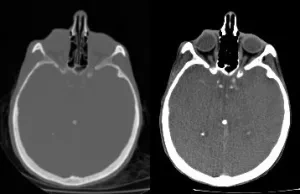

Snímka ľudskej hlavy vytvorená počítačovým tomografom. Kosť je svetlá, mäkké tkanivá sú sivé. Vľavo je neupravená snímka, vpravo kontrast upravený na skúmanie mäkkých tkanív.